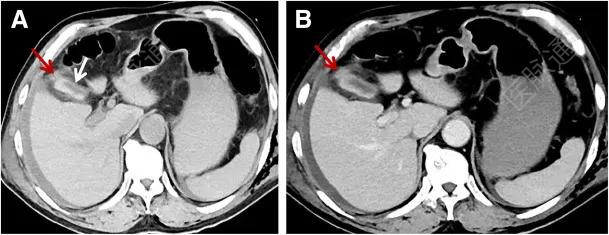

随后行腹部增强CT以进一步评估,CT图像如图A、B所示。

图A、B

患者最可能的诊断结果为?